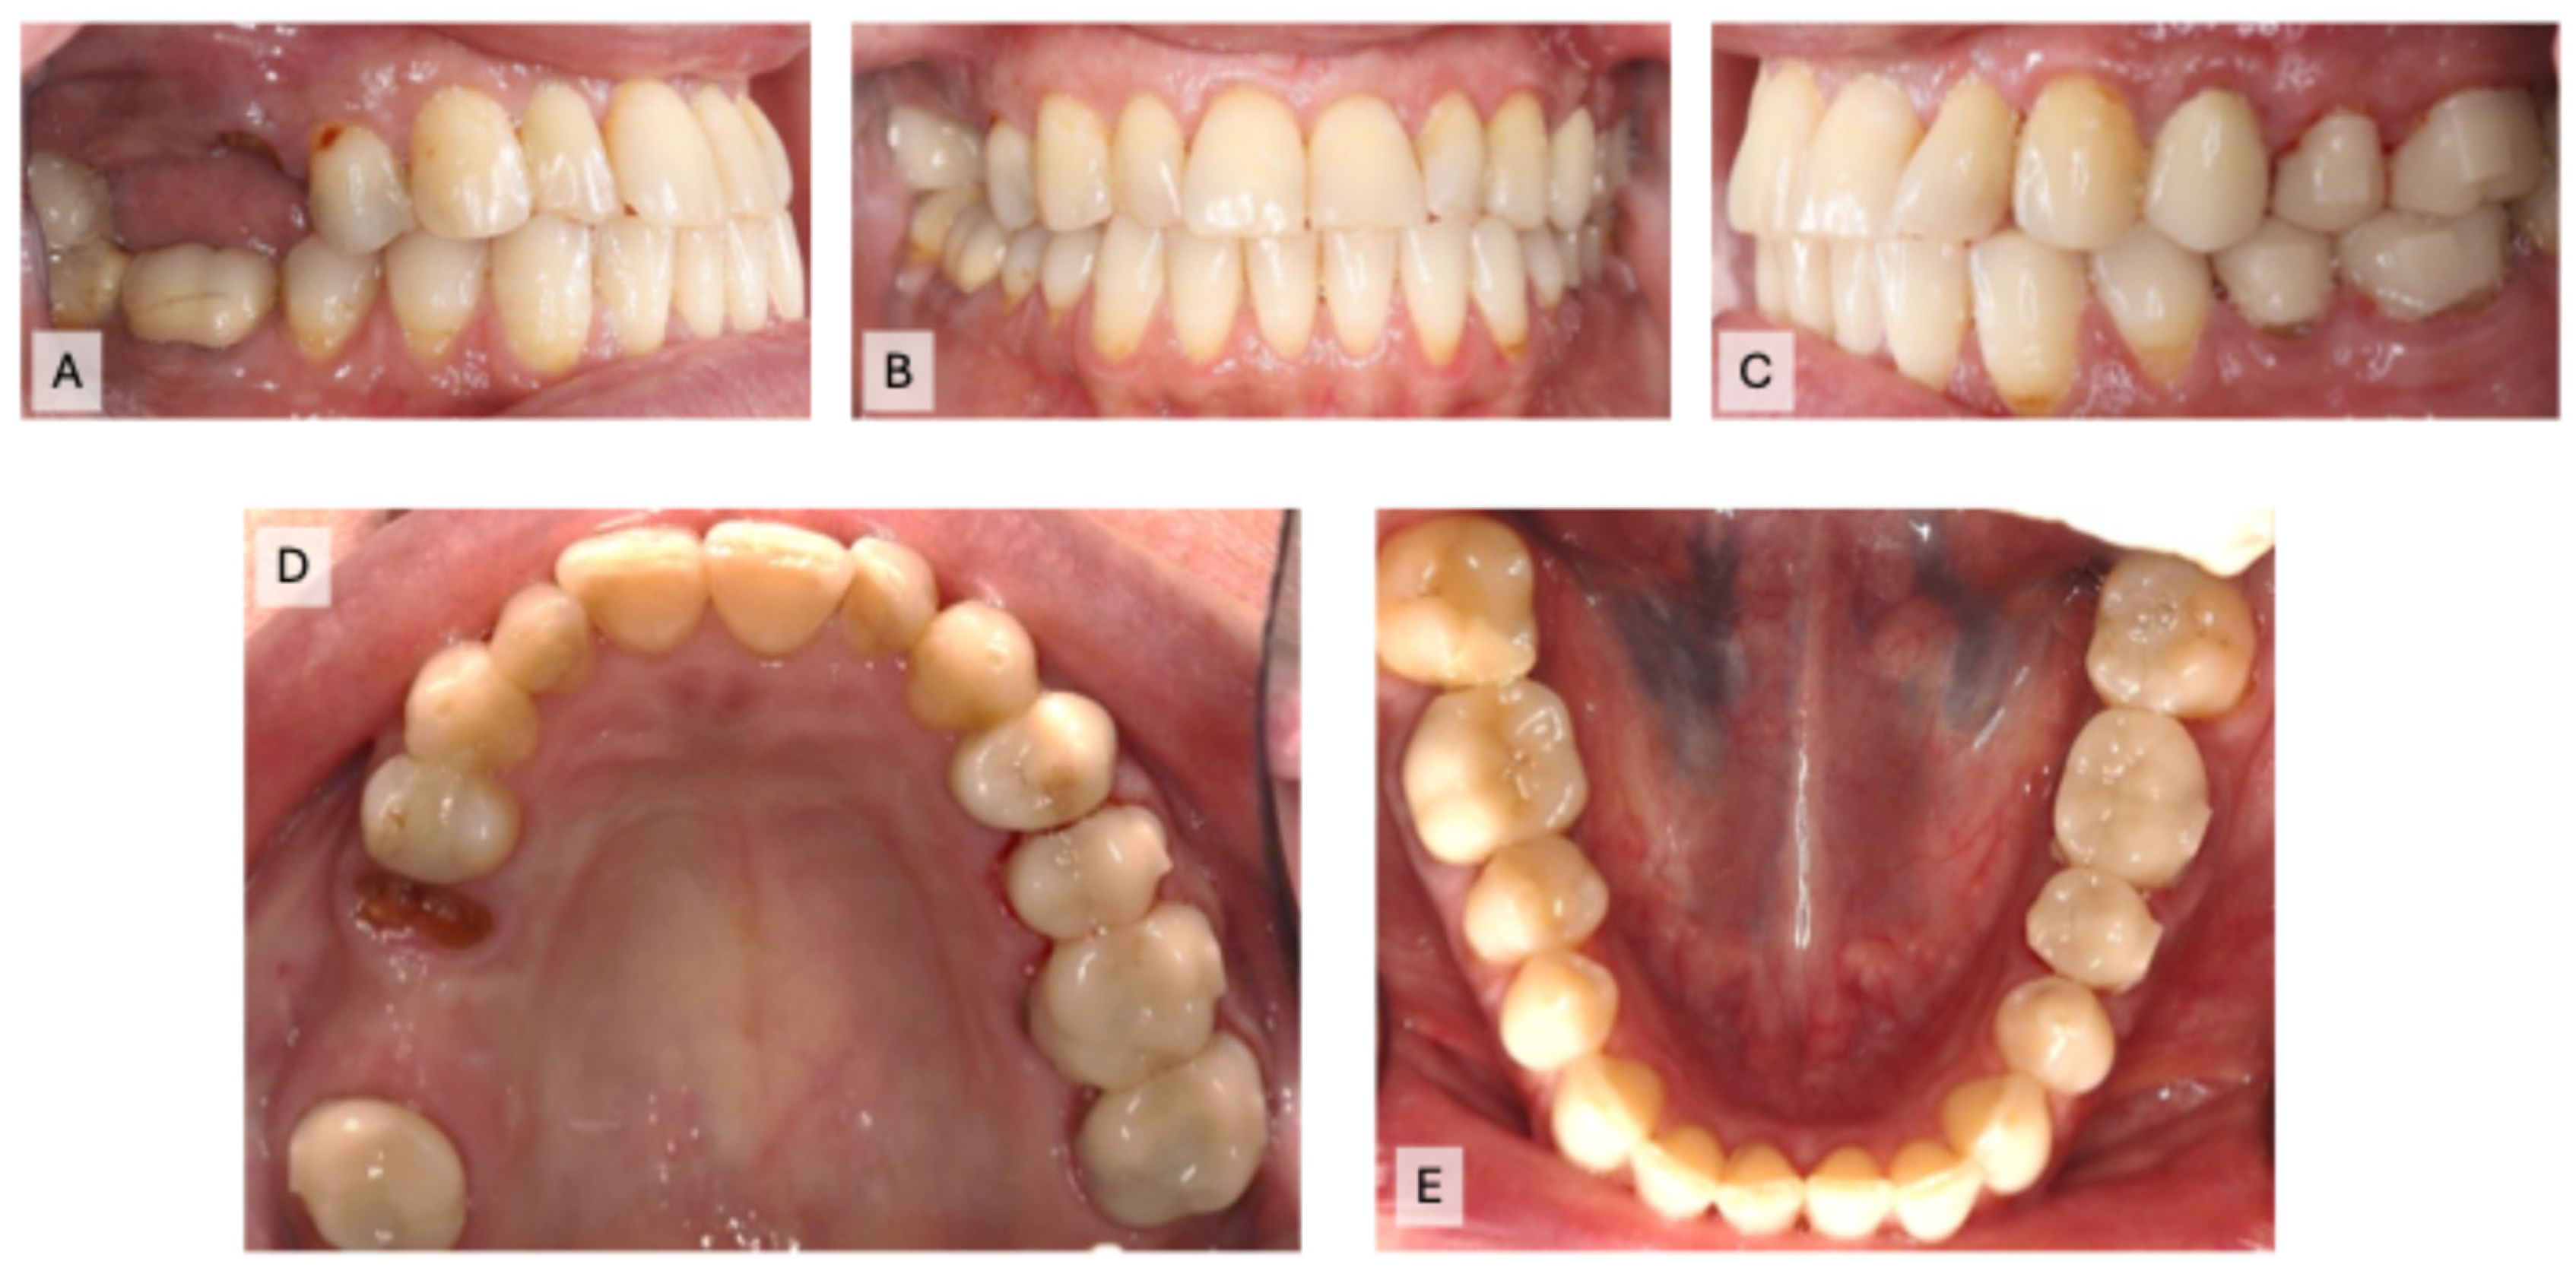

A 49-year-old Saudi female patient came to the orthodontic faculty clinics at Imam Abdulrahman bin Faisal University Dental Hospital with a complaint: “My teeth are crooked, and I would like to correct them”. Her medical history showed no significant findings. Her dental history showed multiple restorations and missing teeth. Upon clinical examination, multiple caries lesions, generalized calculus deposition, generalized gingival recession, a missing tooth (#3), two 3-unit FPDs on teeth #2, X, 4, & 13, X, 15, crowns on teeth #12, 19, 20, and 30, Class I malocclusion, an overjet range from 0 to 1 mm, a shallow overbite of 0–1 mm, a shifted lower midline of 1 mm, 3 mm upper crowding, and 1 mm lower crowding were found. The lateral cephalometric radiograph suggested a normodivergent pattern, with a Class III skeletal relation complicated by the retrognathic maxilla and proclined upper and lower incisors (Figure 1A–E and Figure 2A,B).

Figure 1.

The initial intraoral photographs before restorability assessments: (A) right occlusion; (B) front occlusion; (C) left occlusion; (D) maxillary occlusion; (E) mandibular occlusion.